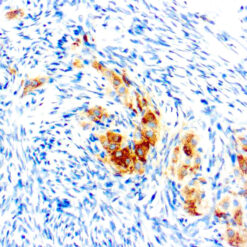

This MAb recognizes human 17-26kDa protein, which is identified as cytokine TNF-α (Tumor Necrosis Factor-alpha). Monomeric human TNF-α is a 157 amino acid protein (non-glycosylated) with a reported molecular weight of 17 kDa and can be expressed as a free molecule, also TNF-α is generated as a precursor form called transmembrane TNF-α can be expressed as a cell surface type II polypeptide consisting of 233 amino acid residues molecular weight 26 kDa. TNF-α is an important cell-signaling component of the immune system. It is a protein secreted by LPS stimulated macrophages, and causes tumor necrosis when injected into tumor bearing mice. TNF-α is currently being evaluated in treatment of certain cancers and AIDS Related Complex.

| Positive Control Tissue | Colon, Histiocytoma, Pancreas |